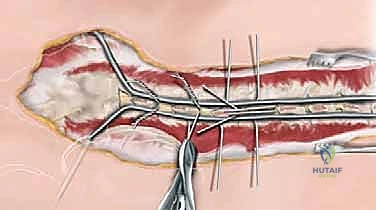

Once the rod is approximated to the spine, the sublaminar wires are sequentially tightened around the rod.

Tightening begins at the apex of the curve to draw the spine to the rod, and then proceeds proximally and distally. The wires must be tensioned symmetrically to avoid asymmetric pull-out.

The wire ends are cut short and meticulously bent over the rod to prevent soft tissue irritation.